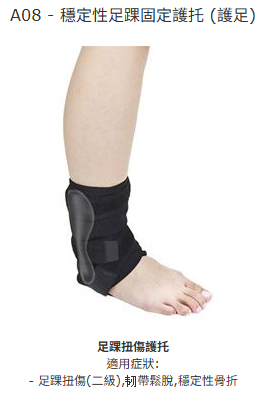

足踝扭傷護托

適用症狀:

- 嚴重足踝扭傷,韌帶撕裂,穩定性骨折

- 足踝扭傷,韌帶鬆脫,預防運動創傷

- 足踝扭傷(二級),韧帶鬆脫,穩定性骨折